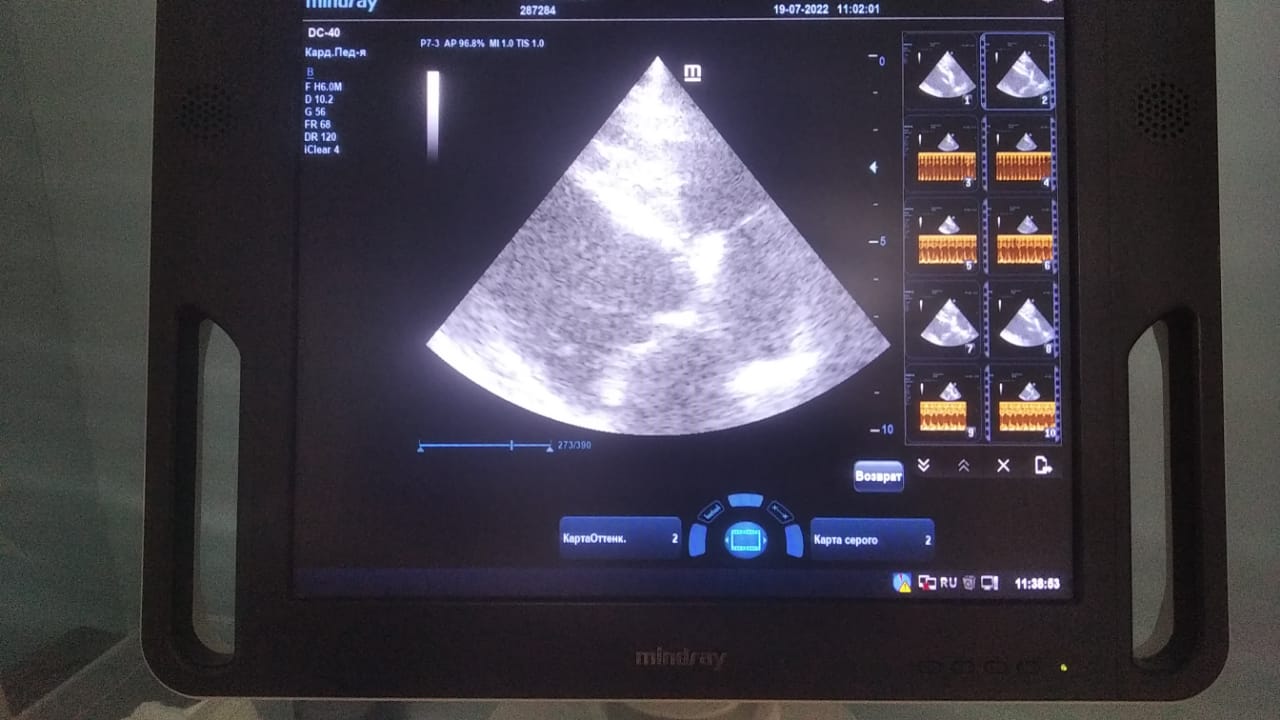

Анализы Арчи. Сердца и легких

Вложения

IMG-20220719-WA0100.jpg

IMG-20220719-WA0102.jpg

IMG-20220719-WA0104.jpg

IMG-20220719-WA0103.jpg

IMG-20220719-WA0105.jpg